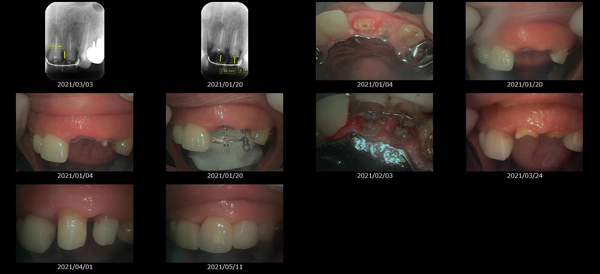

救歯MTMについて

虫歯が大きくて残せない歯、転倒などの事故により歯が根の深いとこで折れてしまったなどで、抜かざるを得ない歯を、骨の中に埋まっている健全な根を、骨の上に矯正的に引き上げることで、その歯を抜かず温存、救歯できる可能性のある治療方法です。

救歯治療と審美性の両立